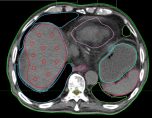

(1)、病例展示一:巨块型肝细胞肝癌合并门静脉癌栓

确诊肝癌并治疗后4月余复诊,伴有高热。腹部核磁:肝右叶异常强化灶,考虑肿瘤性病变;门静脉右支及门静脉主干管腔内见低密度影填充,考虑栓子形成。

病理诊断:肝细胞肝癌。治疗方案:碳离子放疗,总剂量:PTV:70Gy(RBE)/10Fx。同步治疗:阿替利珠单抗注射液+甲磺酸仑伐替尼胶囊。

影像学对比